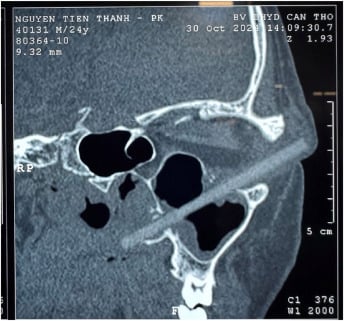

For at komme til bunds i mysteriet foretog lægerne en røntgenscanning – og her dukkede noget bemærkelsesværdigt op:

Dybt i øjenhulen gemte sig et fremmedlegeme på hele 7,6 centimeter. Genstanden havde beskadiget vævet omkring øjet og strakt sig helt ind i bihulerne.

En nærmere gennemgang af scanningen afslørede endelig årsagen: Fremmedlegemet var en splint fra en træspisepind.

Utroligt nok var den trængt ind gennem det bløde væv uden at beskadige selve øjet. Pinden, som var blevet brugt til at spise med, havde dog ført til betændelse og hævelse i området.